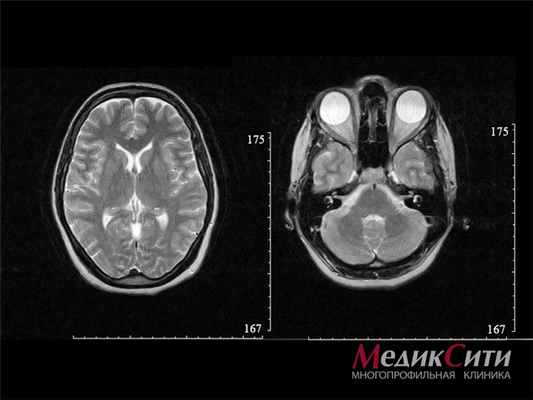

МРТ головного мозга

Для диагностики всех видов черепно-мозговых травм самыми информативными являются рентген и магнитно-резонансная томография. Это позволяют исключить перелом костей черепа.

- КТ и МРТ;